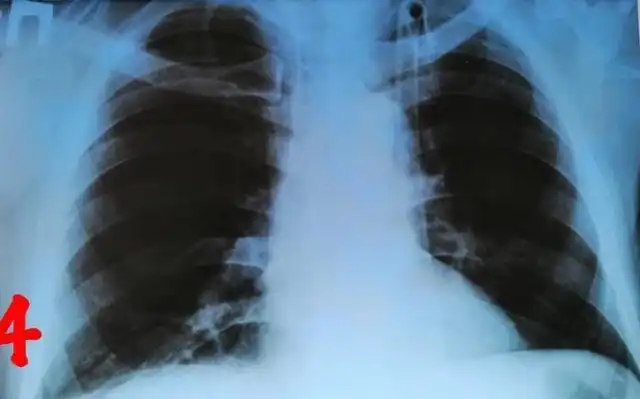

Врачи в Кабардино-Балкарии провели успешную операцию по извлечению пули из груди мужчины, который прожил с ней более 30 лет. По словам медиков, мужчина 1954 года рождения поступил в отделение с жалобами на ноющую боль в области груди, которая началась около месяца назад. Сделав рентгеновские снимки, медики обнаружили инородный предмет в грудной полости.

Как стало известно во время операции, инородным телом оказалась пуля. По словам медиков, она находилась в теле пациента уже более 30 лет, но начала создавать дискомфорт лишь некоторое время назад, когда сдвинулась с места.

Пациента уже выписали и отпустили домой. Каким образом пуля попала в тело мужчины, врачи не уточнили.